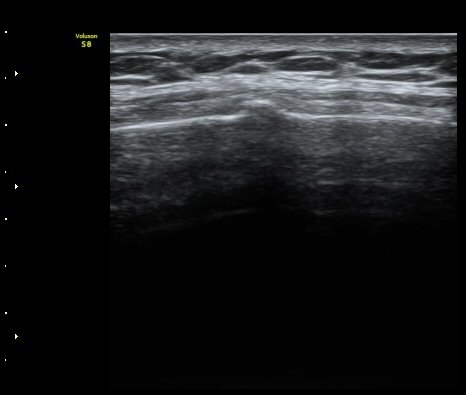

°¥ºñ»À Ⱦ´Ü¸é°Ë»ç¿¡¼­ °¡°ñ Çü¼ºÀÌ °üÂûµÊ(formation of callus)   »çÁø 4

°ñ À¯ÇÕÀÌ È®ÀεÊ.